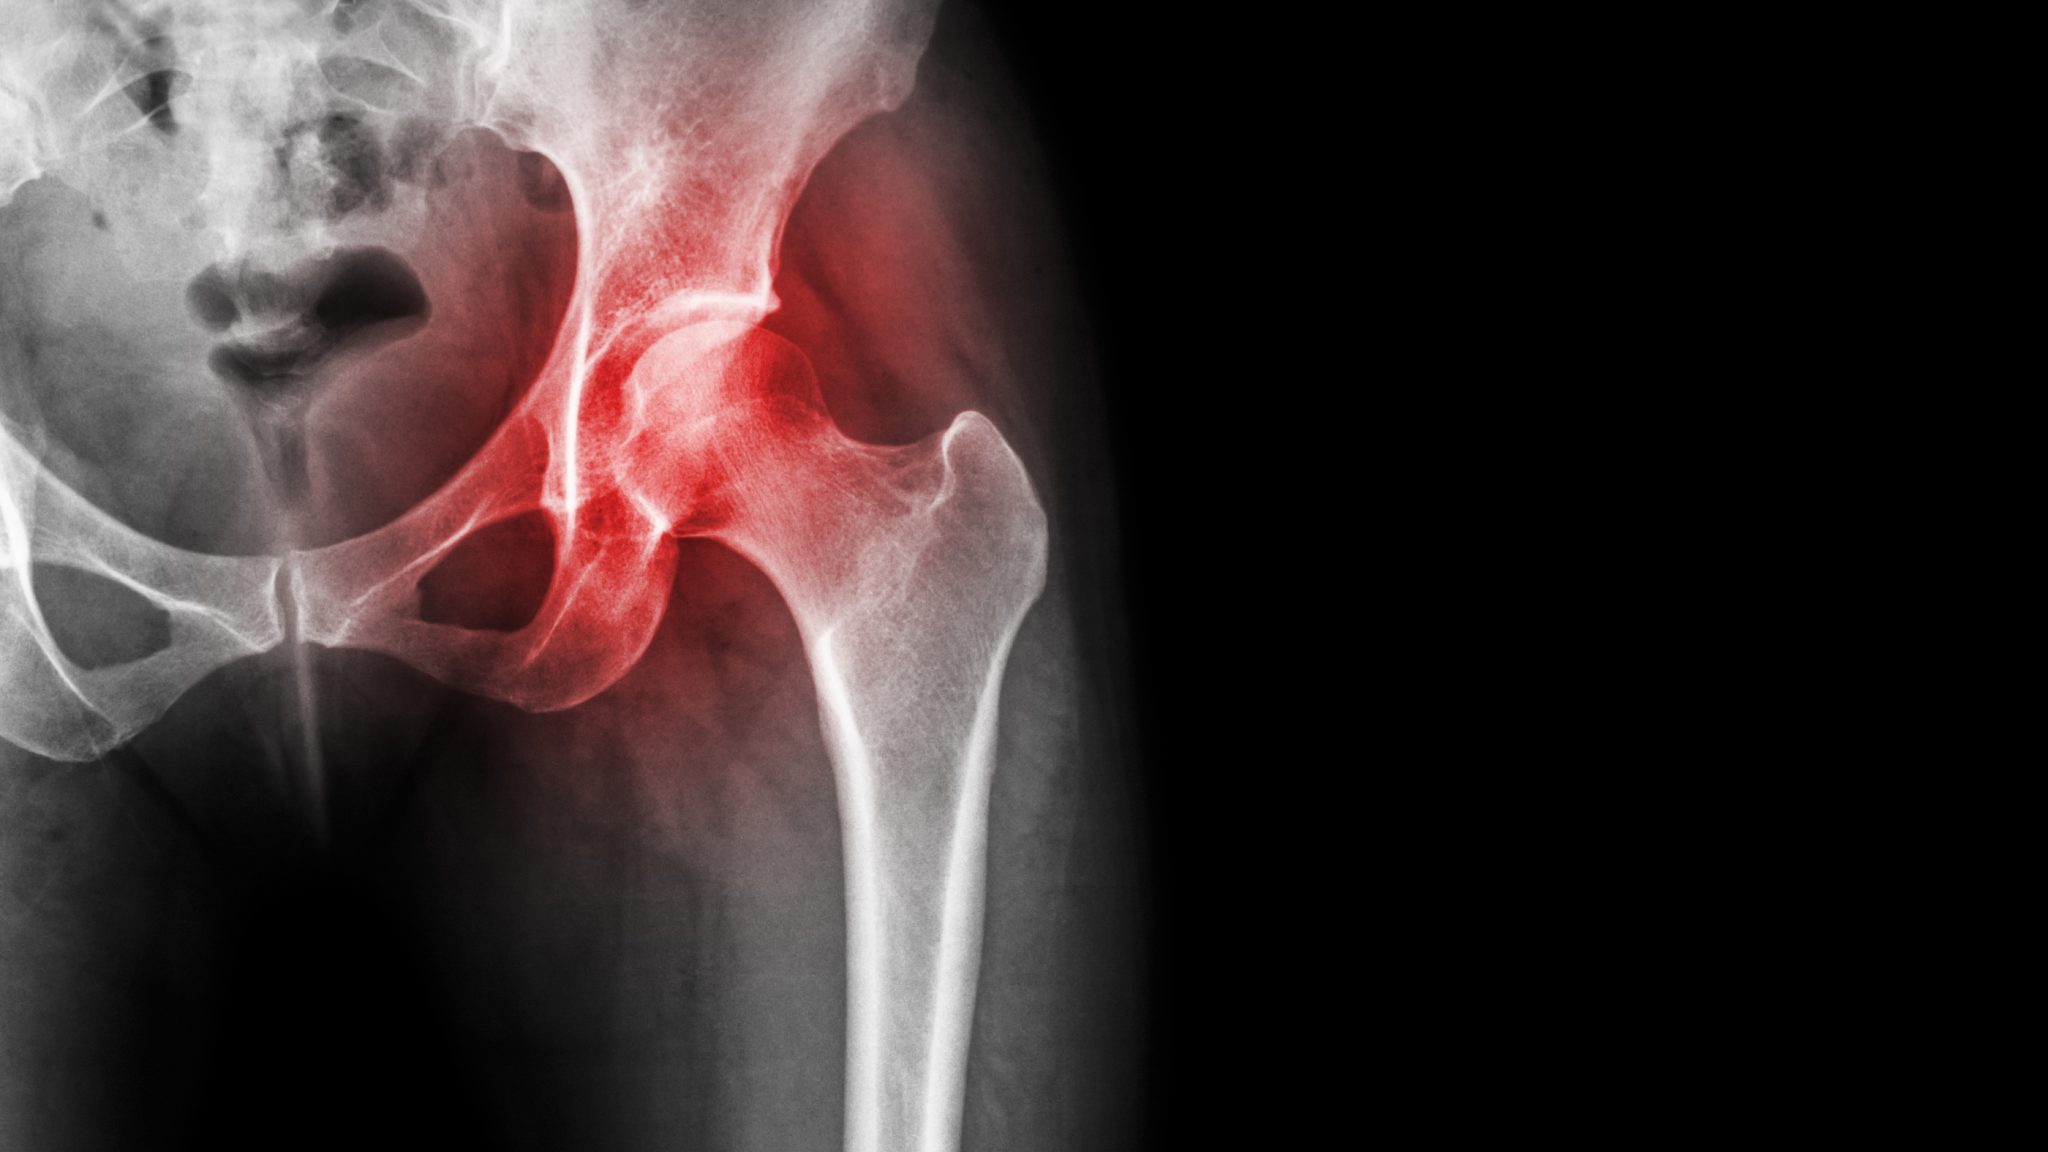

Understanding avascular necrosis of the hip Orthopedic Center for Sports Medicine Sports What Is An Avascular Mass  It can be cancerous or benign depending on the. A hypoechoic mass is a darker area in an organ or tissue that is seen on ultrasound. The avascular and vascular phases of solid tumor growth on the basis of the experiments discussed above, the growth of. Learn how to diagnose and manage common and rare soft tissue masses, including benign. What Is An Avascular Mass.

Avascular Necrosis Of The Hip SurgiTEN Specialists What Is An Avascular Mass  It can be cancerous or benign depending on the. The avascular and vascular phases of solid tumor growth on the basis of the experiments discussed above, the growth of. Find out the signs, symptoms, imaging, and treatment options for. A hypoechoic mass is a darker area in an organ or tissue that is seen on ultrasound. Isoechoic is an ultrasound. What Is An Avascular Mass.

Avascular Necrosis (AVN) of the Femoral Head Findings on XRay Calgary Guide What Is An Avascular Mass  A hypoechoic mass is a darker area in an organ or tissue that is seen on ultrasound. It can be benign or cancerous and does not imply. The avascular and vascular phases of solid tumor growth on the basis of the experiments discussed above, the growth of. Isoechoic is an ultrasound term that means a tissue or structure has the. What Is An Avascular Mass.